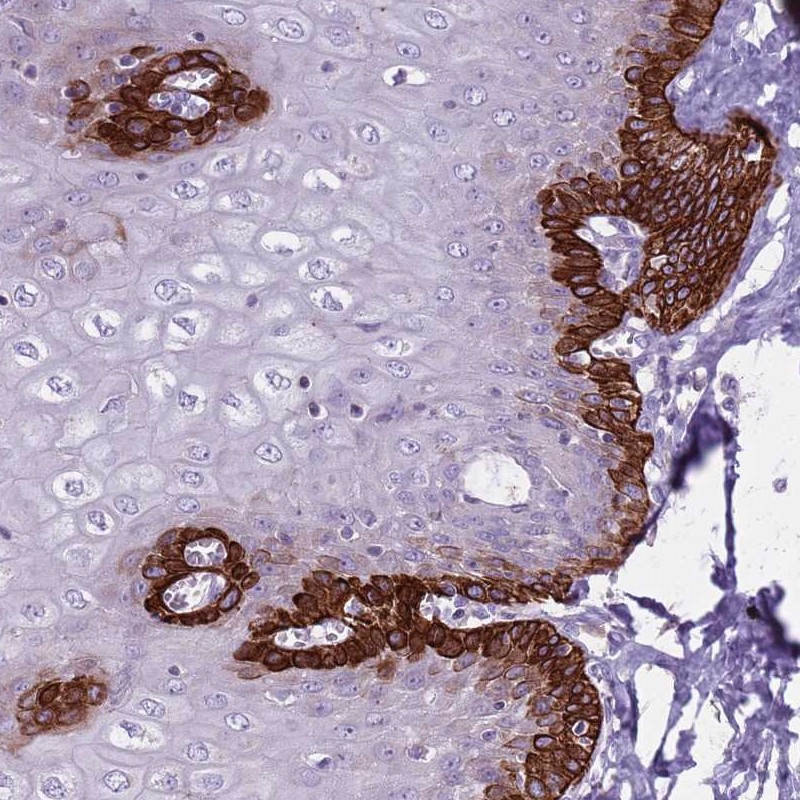

Immunohistochemical staining of human esophagus shows strong cytoplasmic positivity in basal cells of squamous epithelia.